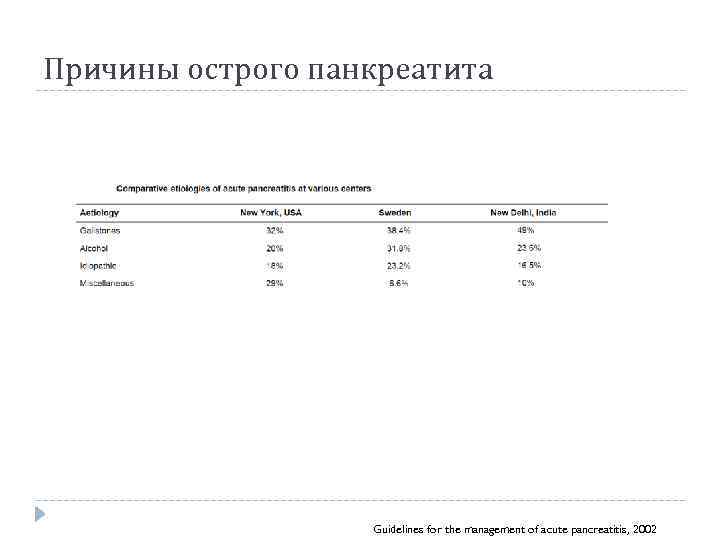

Причины острого панкреатита Guidelines for the management of acute pancreatitis, 2002

Причины острого панкреатита Guidelines for the management of acute pancreatitis, 2002